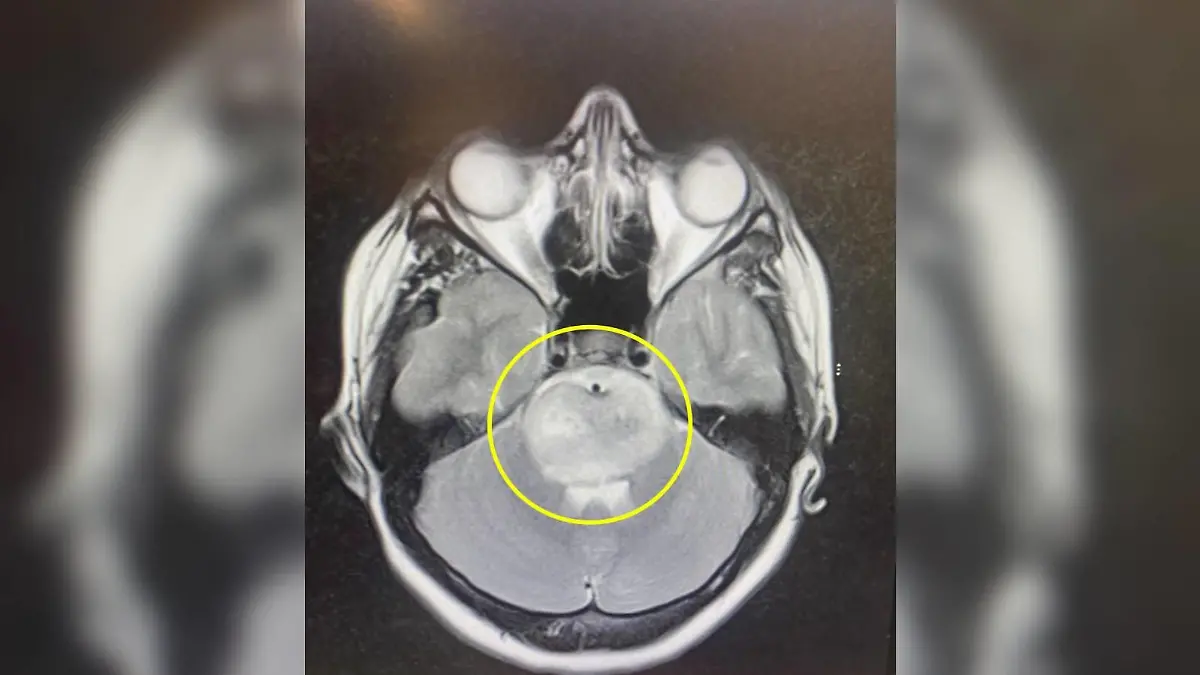

Nach einem weiteren besonders starken Migräneanfall sei Ella im Juli 2023 ins Krankenhaus gekommen, wo Ärzte einen Knoten in ihrem Gehirn entdeckten – ein diffuses Mittelliniengliom. Laut dem Deutschen Krebsforschungszentrum zählt das diffuse Mittelliniengliom zu den aggressivsten Hirntumoren. Chemo- oder Strahlentherapie seien nur begrenzt wirksam.

Wie lange genau Ella noch leben wird, können die Ärzte nicht sagen. Dazu brauche es eine Biopsie, die man aber wegen der Lage des Tumors nicht durchführen könne. Zu groß sei die Gefahr, Ella bei dem Eingriff zu lähmen.